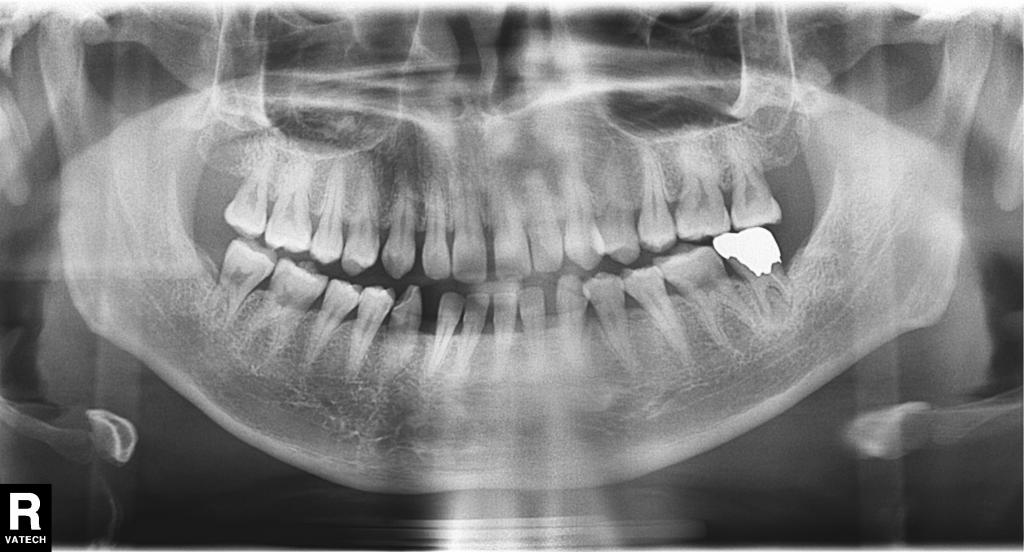

- レントゲン写真で見ると、この7番の部分の歯の周りの骨が大きく吸収しているのが分かりました。

これだけ吸収(溶けている)していると、治療しても必ず良くなるかどうかは断言できないことをお話しして、治療を行いました。